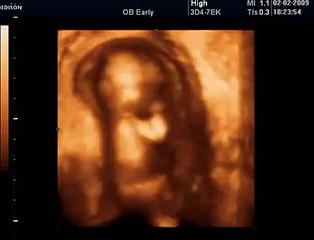

BCF Ultrason Görüntüsü - Hasvet Medikal